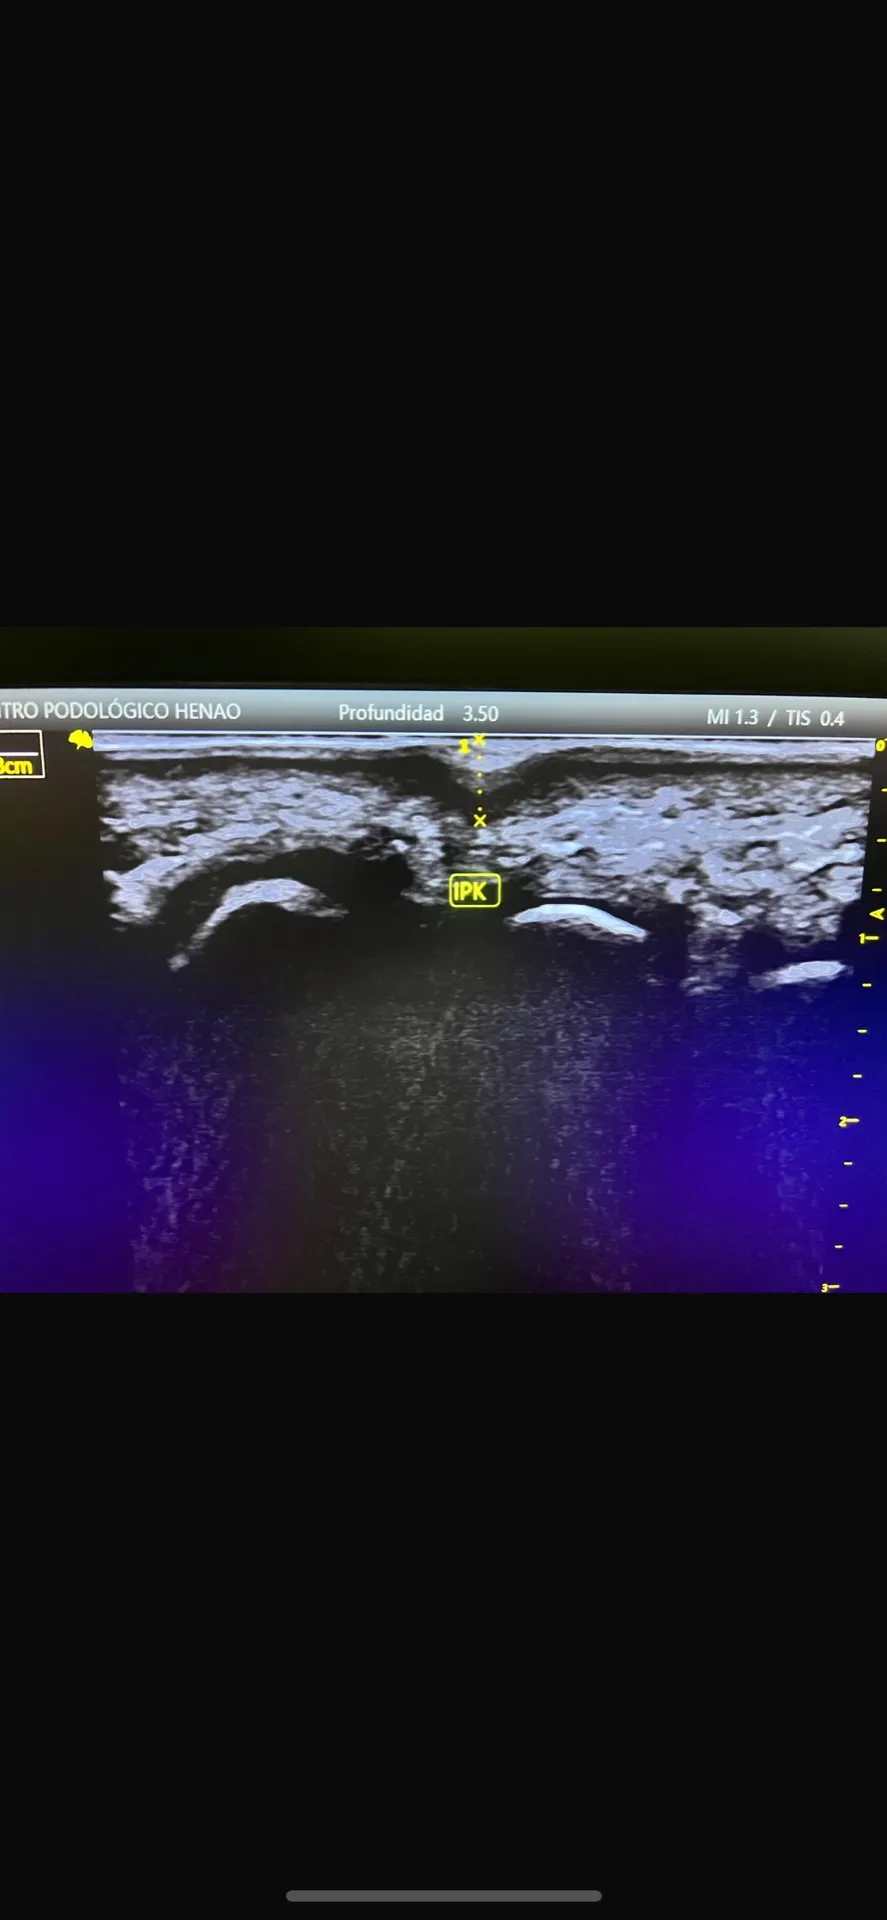

Figura 6: El estudio ecográfico nos permite ver estructuras que no son visibles a simple vista y planificar el tratamiento con precisión.

Utilizamos plataforma de presiones computarizada, análisis de la marcha, evaluación del rango de movimiento articular, y cuando es necesario, ecografía musculoesquelética para comprender exactamente qué está causando la hiperpresión.